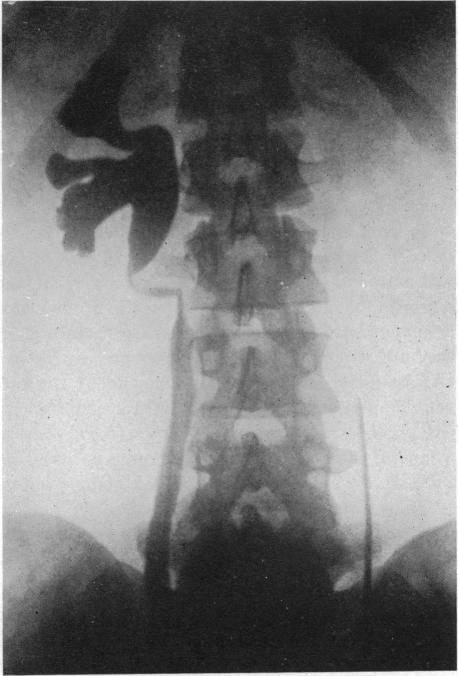

STRICTURE OF THE URETER.

Ann Surg. 1925 Apr;81(4):839-50. doi: 10.1097/00000658-192504000-00013.